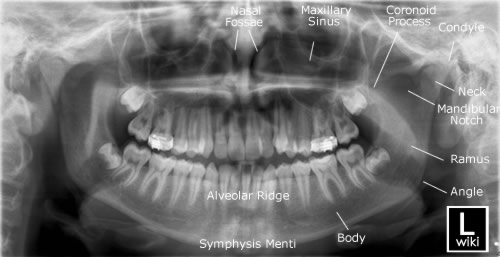

Panoramic X Ray Anatomical Landmarks - These Normal Radiographical Anatomical Landmarks Are Unique To Each Area Of The Maxilla Or Mandible And Appear Either Radiopaque Or Radiolucent.

Anatomical structures facilitates diagnosis and registration of dental records.

This method is useful in providing diagnostic information regarding identifiable landmarks because of a lack of three dimensional viewing, panoramic view provides limited information regarding anatomical limitations. Landmarks were selected to be clinically meaningful and clearly identifiable in 3d; Of reference anatomical landmarks in order to achieve accurate and undistorted panoramic. Automatic segmentation of mandible in. I was asked by representatives from panoramic corporation. Anatomical structures facilitates diagnosis and registration of dental records. Landmarks common to both the maxillary and mandibular radiographs.

External auditory meatus (external acoustic meatus). It is important to understand the landmarks normally seen on panoramic images in order to prevent misdiagnosis of a radiopaque or radiolucent area. Landmarks common to both the maxillary and mandibular radiographs. Panoramic radiography is a form of tomography; New and refurbished panoramic dental x ray machines for sale, including panoramic xray, panorex machine or panoramic x ray machine for sale at low prices. ๐Ÿ‘‰ enumerate all radiolucent landmarks visible on a panoramic radiograph. This study presents a fast and. 39 companies | 109 products. This method is useful in providing diagnostic information regarding identifiable landmarks because of a lack of three dimensional viewing, panoramic view provides limited information regarding anatomical limitations. The maxillary and mandibular anatomical structures such as pterygomaxillary fissure, incisive foramen mandibular canal, anterior loop of mental nerve and mental foramen were analysed. Automatic segmentation of mandible in. Of reference anatomical landmarks in order to achieve accurate and undistorted panoramic. I was asked by representatives from panoramic corporation. Accurate method for automatic segmentation of mandible in. Anatomical structures facilitates diagnosis and registration of dental records. Bony landmarks of the maxilla and surrounding structures: Anatomical landmarks (panoramic) learn by taking a quiz. This radiopaque landmark is only seen on a panoramic radiograph and is just anterior to the mandibular foramen. 0 ratings0% found this document useful (0 votes). * prior to any kind of surgery in the maxillofacial region, opgs are made to assess the anatomical location of various clinically important structures. Cephalometric analysis is an essential clinical and research tool in orthodontics for the orthodontic analysis and treatment planning. Learn vocabulary, terms and more with flashcards, games and other study tools. Dental panoramic x ray landmarks. Genial tubercles the genial tubercles are small bony spines found on the 35. Start studying panoramic normal anatomical landmarks. Thus, images of multiple planes are taken to make up the composite panoramic image. External auditory meatus (external acoustic meatus). Landmarks were selected to be clinically meaningful and clearly identifiable in 3d; Savesave anatomical landmarks of panoramic radiographs for later. Visibility of mandibular anatomical landmarks in panoramic radiography: Orthopantomogram procedure, uses and costs.